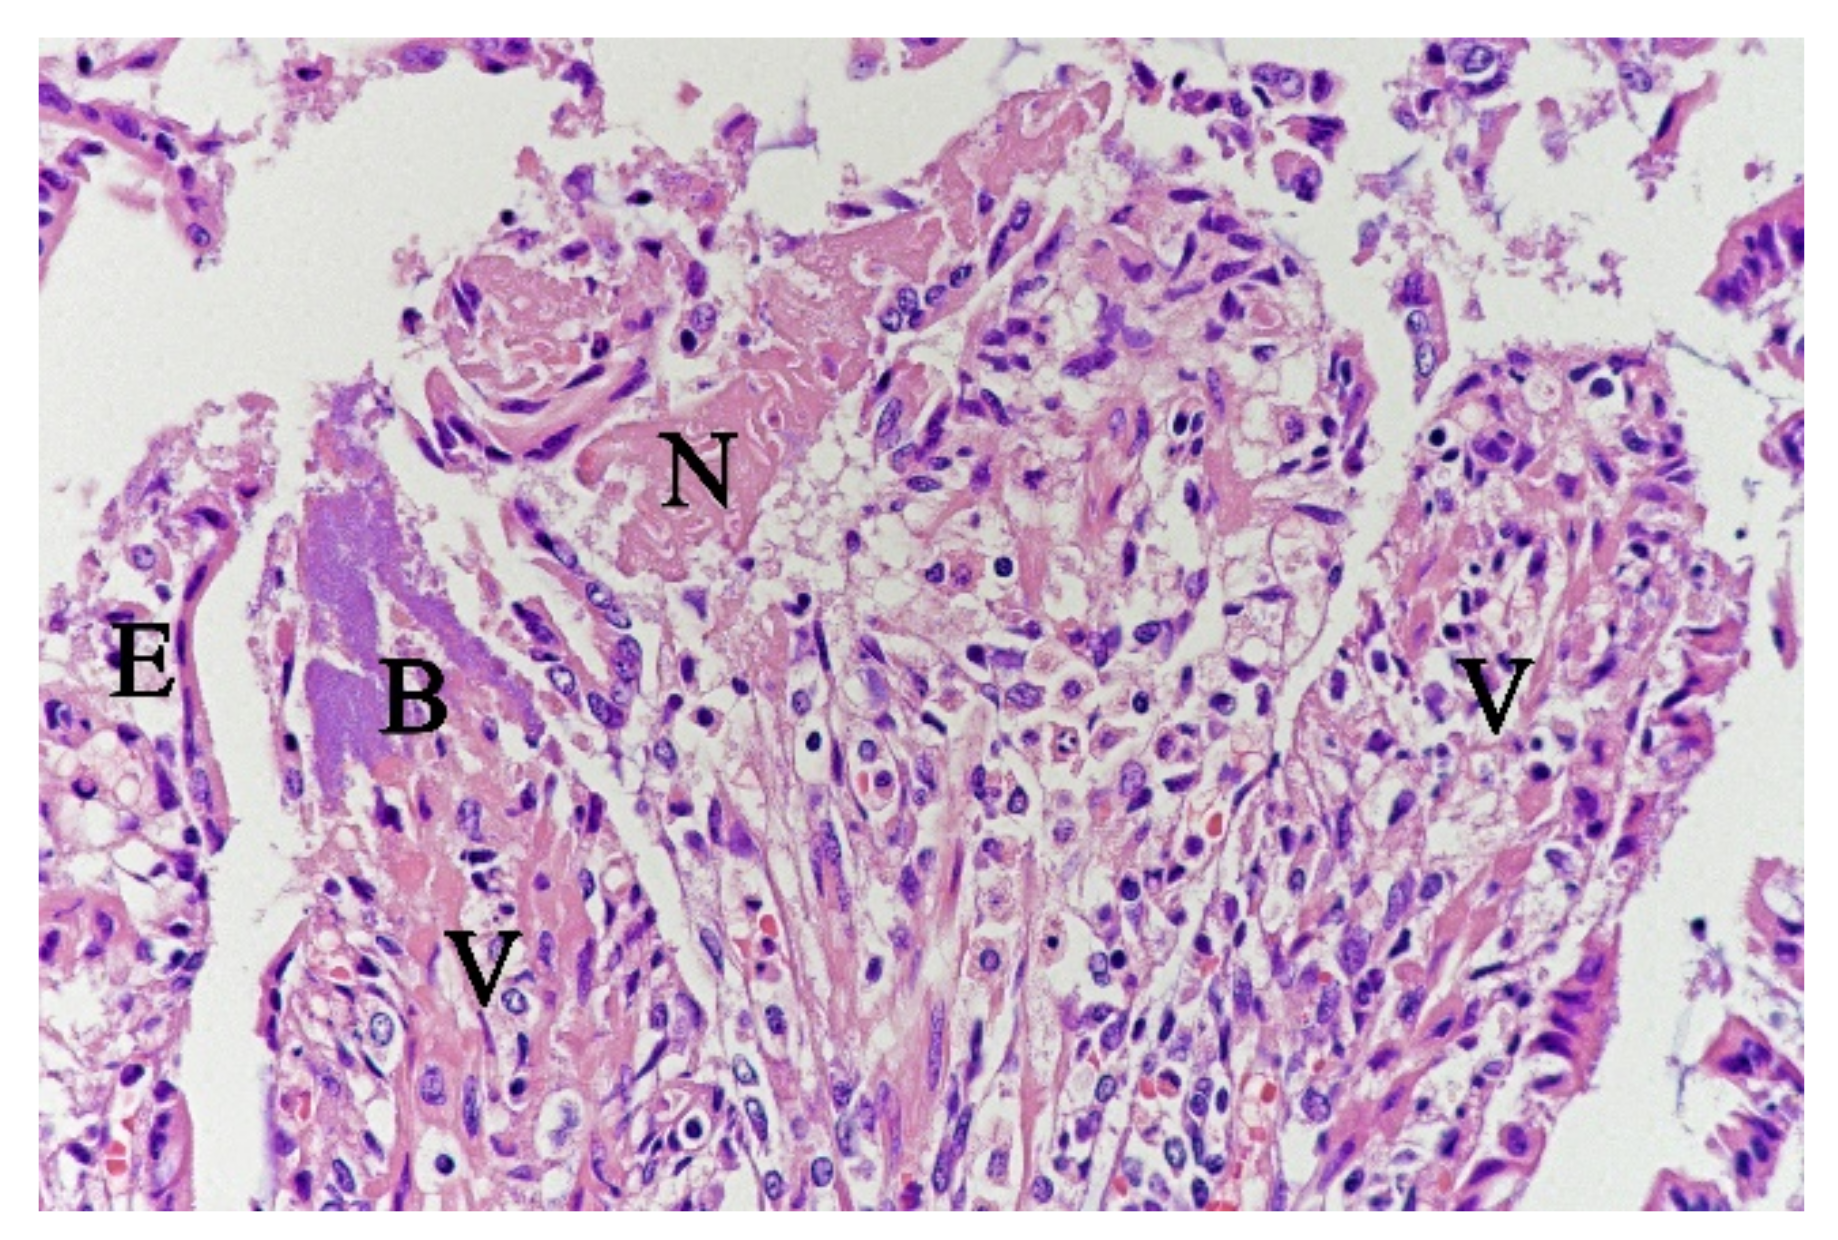

Figure 4.

Histological section from small intestine dog with acute haemorrhagic diarrhoea, HE-stain. There was a loss of surface epithelium, necrotic epithelial cells (N), and elongated/stretched epithelial cells (E) trying to cover lamina propria. Note the abundance of bacteria (B) in a necrotic area on one of the villi (V).

In contrast, the small intestinal mucosa showed dramatic changes with diffuse loss of surface epithelium and loss of architecture with collapse of the villi lamina propria. In some of the dogs, necrosis of intestinal epithelial cells was observed, and multifocal haemorrhages were seen in the deep lamina propria and submucosa (Figure 4). Gram-stained sections showed rich amounts of small Gram-negative rods, located as single bacteria or thick layers close to the surface or as larger clusters deeper in the collapsed lamina propria (Figure 5). Additionally, varying, but often rich amounts of large Gram-positive rods often adherent to the denuded or naked remnants of the villi lamina propria, were observed. The histopathological changes in the large intestine were similar to the findings in the small intestine, with the observation of the same types of bacteria on the surface and in the lamina propria.